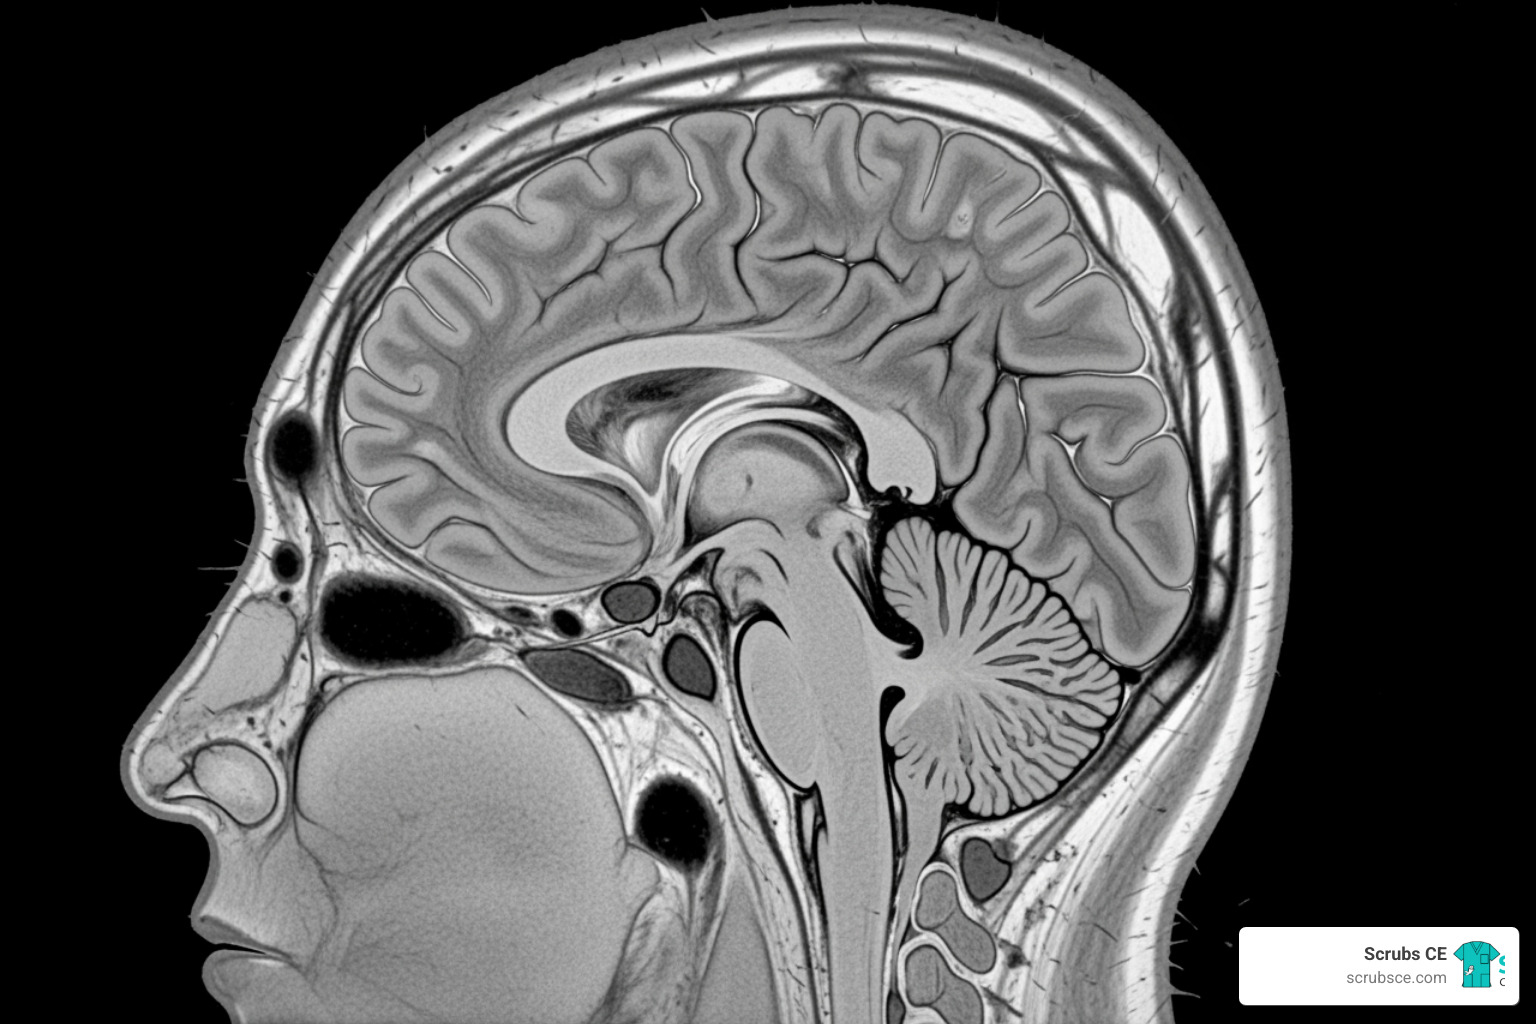

Magnetic Resonance Imaging (MRI) uses magnetic fields and radio waves, not radiation. It interacts with hydrogen atoms in water, providing excellent soft tissue contrast. Key sequences include: T1-weighted images, where fat is bright (hyperintense) and fluid is dark (hypointense), showing great anatomical detail. T2-weighted images, where fat and fluid are bright, are excellent for spotting pathology like inflammation. MRI is the top choice for neurological and musculoskeletal imaging.

On brain MRI, T1w images show fat as bright and CSF as dark, providing excellent anatomical detail. On T2w images, both fat and fluid are bright, highlighting pathology like edema or inflammation. Head CT is vital for trauma. We use bone windows to see the skull base, orbits, and paranasal sinuses for fractures, and soft tissue windows to evaluate brain parenchyma for hemorrhage or mass effect. Neck CT reveals the cervical spine, thyroid gland, and major blood vessels. The Anatomy Coloring Workbook can help reinforce these complex relationships.

Why are anatomical planes crucial for interpreting CT and MRI scans?

Anatomical planes are the coordinate system for cross-sectional imaging, allowing you to mentally reconstruct 2D slices into a 3D visualization.

The axial, sagittal, and coronal views each provide a unique perspective on the same anatomy. Understanding which plane you are viewing is essential for lesion localization. By tracking an abnormality across different planes, you can pinpoint its exact 3D location and its relationship to surrounding structures.

This precision is vital for surgical planning, as surgeons need a detailed roadmap. It also enables clear communication among the healthcare team. Anatomical planes are not just academic; they are the practical framework for navigating the human body in modern imaging.